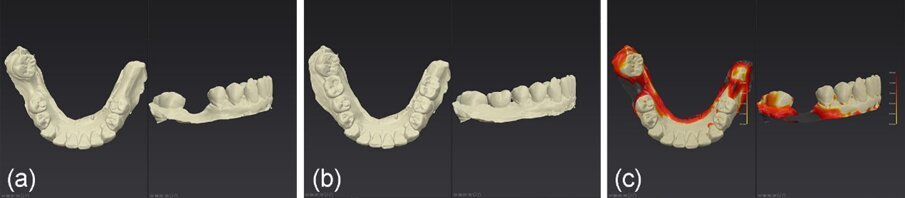

Nel caso 2, il tessuto cheratinizzato è stato preservato anche sui lati vestibolare e linguale a T2 e i valori dell’altezza del complesso sovracrestale erano identici a quelli registrati nel caso 1 (Fig. 26). Per quanto riguarda la valutazione a T3 e dopo l’inserimento di una corona monolitica in zirconia completa a 4 mesi, è evidente che è stata preservata una mimica del profilo cervicale del tessuto molle con conservazione del tessuto cheratinizzato (Fig. 27). Infine, sono state effettuate impronte digitali intraorali utilizzando lo scanner intraorale iTero (Align Technology), a T1 e a T3. I file STL (standard tessellation language) sono stati esportati nel software DTX Studio Clinic (Envista) per la comparazione nel tempo. Sulla base di un algoritmo di informazioni reciproche, le scansioni sono state sovrapposte automaticamente e un codice a colori ha mostrato le aree di differenza (Fig. 27).

Fig. 26_Generazione del profilo cervicale a 4 mesi dopo la rimozione del moncone personalizzato: a) vista vestibolare, b) vista occlusale, c) vista linguale.

Fig. 27_Risultato clinico del sito 46 con corona in zirconia in situ dopo 2 anni e 7 mesi.

Fig. 28_a), b): File STL pre-operatori e a 2 anni e 7 mesi post-operatori esportati nel software DTX Studio; c) i due file STL sovrapposti per ulteriori confronti.